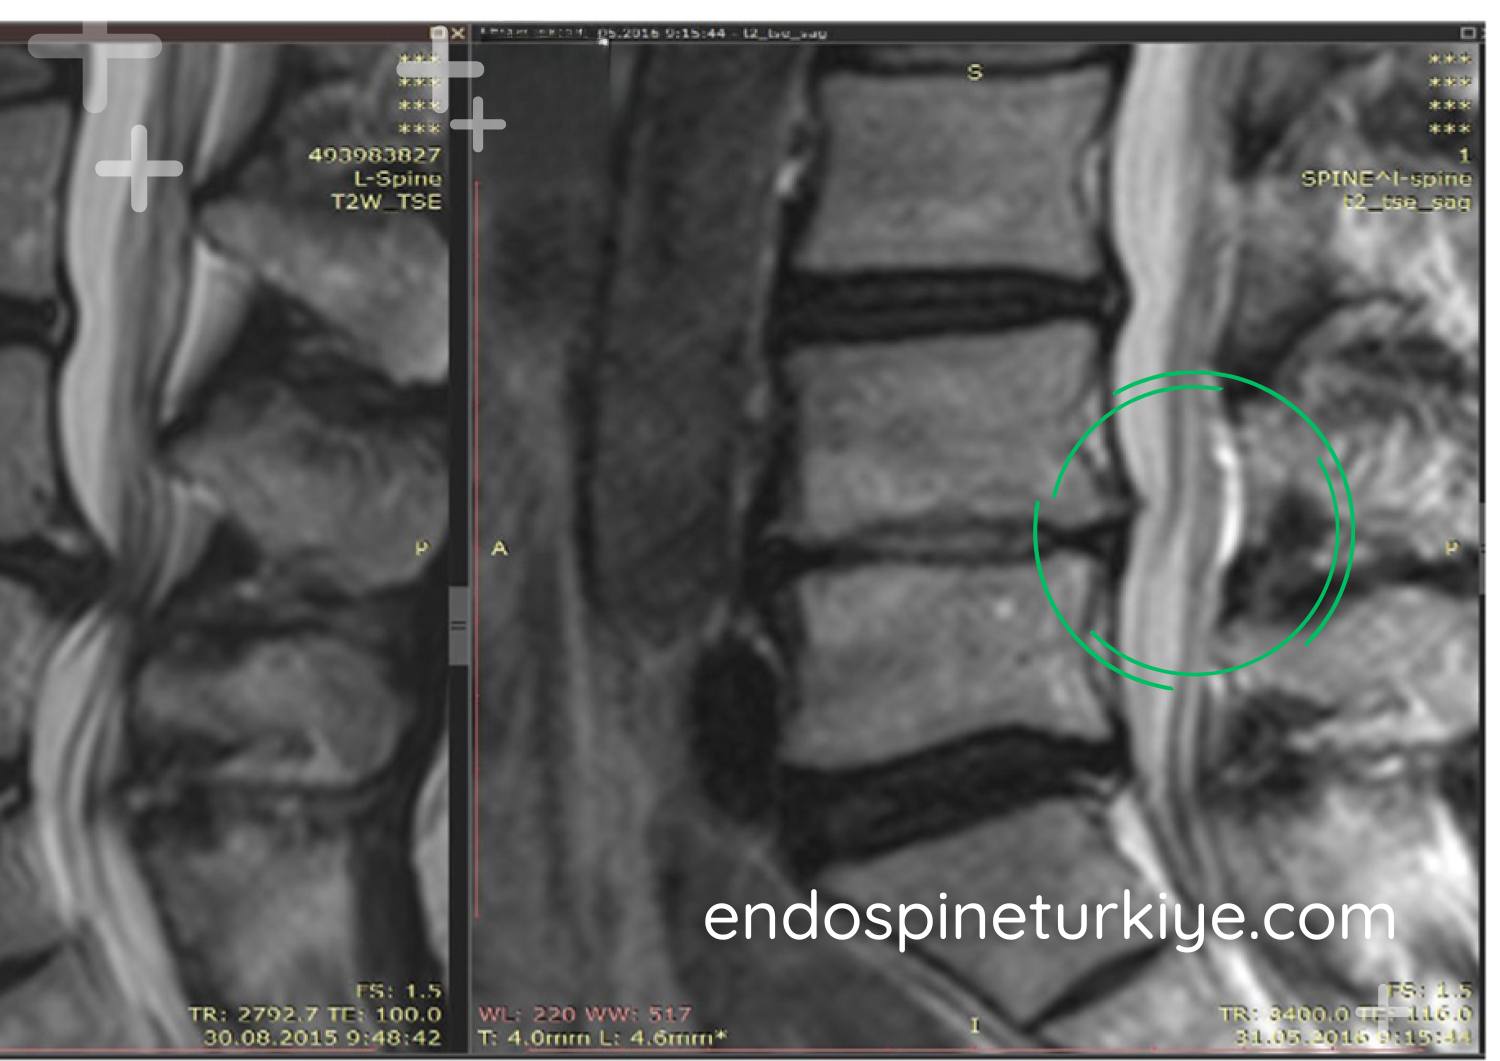

Bel Fıtığı Ameliyatı Öncesi ve Sonrası

Tedavi Öncesi

Tedavi Sonrası

MR görüntülerinde endoskopik bel fıtığı ameliyatı öncesi ve sonrası karşılaştırma